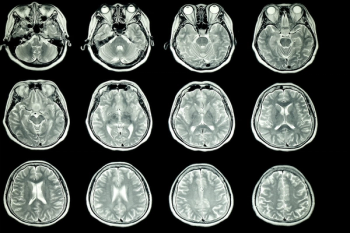

Through AI technology, Neurophet AQUA now provides multiple sclerosis (MS) analysis with a combination of lesion quantification and enhanced segmentation of T2-FLAIR MRI.